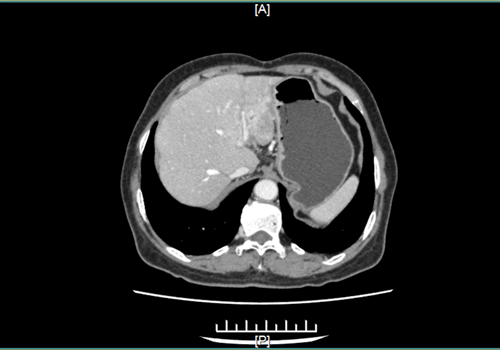

不久前,莉莉的母亲觉得身体不适,“双侧肋骨下隐隐作痛”,在当地医院就诊时,医生建议其做胸部CT。检查结果显示肝区有一个7cm的包块,“当时我就觉得这不是好现象,一定要查明。”莉莉说,于是她带着母亲在当地医院住院。待做完增强CT、MR等检查之后,医生结合病史考虑是良性肿瘤,但肿瘤的大小已经达到手术指征,建议其手术切除。

术前影像图。院方供图

但经过进一步的检查,医生发现莉莉母亲“门脉左外支及肝左静脉受侵”,意思是肿瘤侵犯了肝左静脉。经过几天的术前准备,4月25日下午,一场由刘作金教授主刀、肝胆外科和麻醉科医师密切配合的腹腔镜手术开始了。